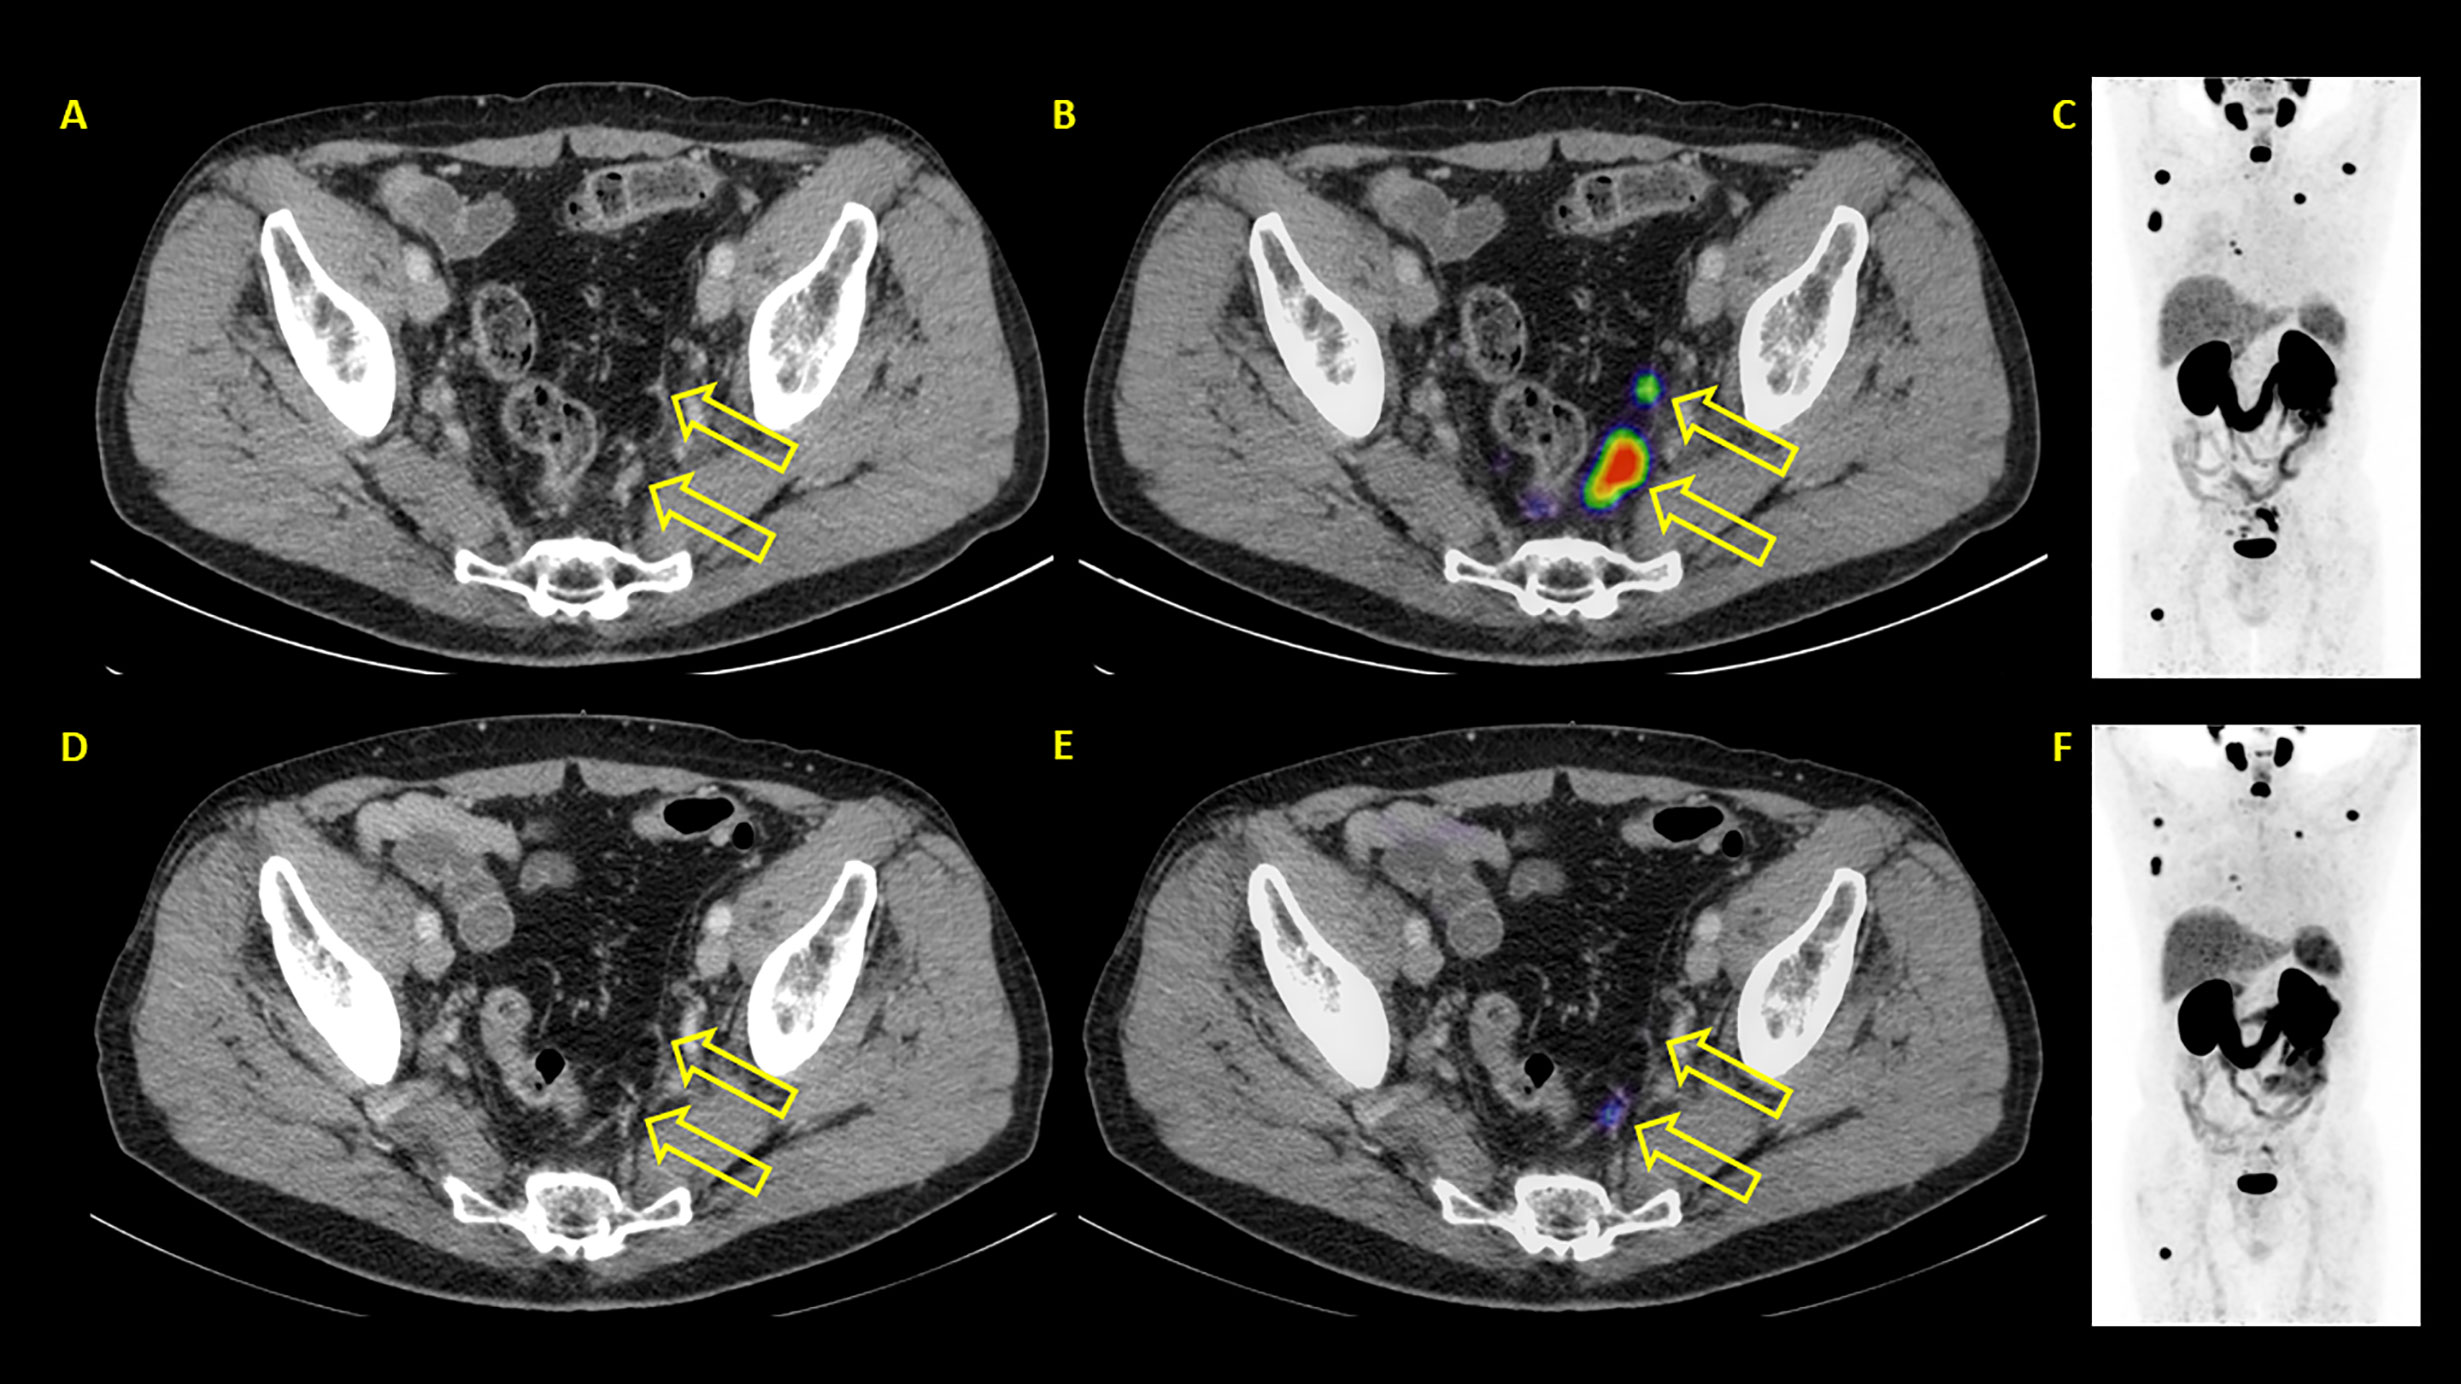

In contrast to PSA response, PSMA PET/CT based response evaluation showed objective response (52.6% PR and 23.7% SD) in about three-fourths of the patients and PD in 23.7%. Figures 5–7 show examples of patients showing concordant and discordant results between PSA and RLT-REC-PCA response. Fendler et al. reported similar results with PR in 27%, SD in 40% (objective response 67%) and PD in 33% of patients based on 68Ga-PSMA PET/CT response assessment in 15 patients after two treatment cycles (19). A direct comparison of our results with previously published data is hampered by the fact that our image based response analysis was based upon RECIST 1.1 with integration PET data for bone metastases assessment whereas Fendler et al. used only measurable CT based assessment excluding bone lesions (16).

Figure 7 Example of a patient where PSA and PET showed discordant results. PSA showed progressive disease with PSA rising from 24.3 to 35.8 ng/ml. PSMA PET/CT showed partial remission. (A–C) represent baseline images whereas (D–F) represent interim PET/CT. (A, D): axial CT slices; (B, E): axial fused PET/CT images; (C, F): maximum intensity projection images.